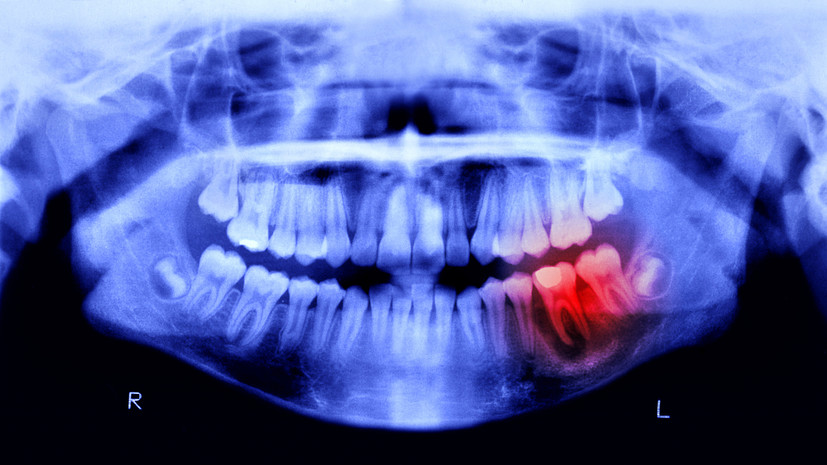

Специалист прокомментировал исследование о связи кариеса с болезнью Паркинсона

Основатель одной из федеральных сетей стоматологических клиник Залим Кудаев рассказал, что новое исследование южнокорейских учёных впервые выявило прямую связь между бактерией Streptococcus mutans, вызывающей кариес, и механизмами развития болезни Паркинсона.

По его словам, при нарушении гигиены полости рта бактерии могут попадать в кишечник, где вырабатывают токсичное соединение имидазол‑пропионат, способное достигать мозга и провоцировать гибель дофаминергических нейронов.

Эксперт добавил, что результаты исследования открывают возможности для профилактики через стоматологическую помощь, а пока клинические приложения находятся в разработке, регулярный уход за зубами становится потенциальным способом защитить мозг.